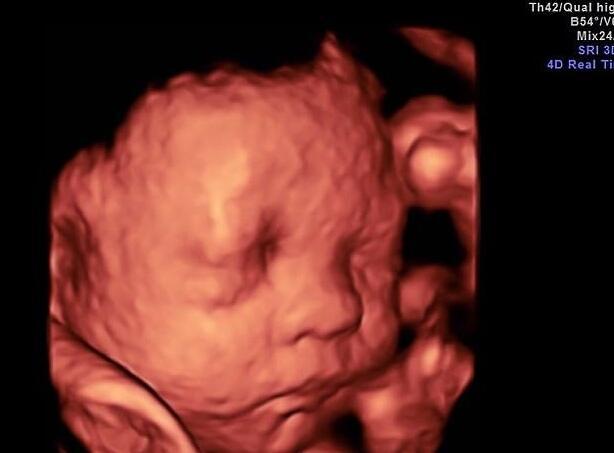

四维彩超主要是为宝宝做一次排畸产检 , 检查胎儿是否有唐氏综合征的情况 。 四维彩超又被称之为“宝宝人生的第一张照片” , 是通过B 超的方式检查的 。

?四维彩超不但要检查胎儿的外形是否畸形 , 还包括心、肝、脾、肺等内脏器官都要检查 , 所以需要胎儿宝宝的配合 。 四维彩超又被称之为“晚期唐筛” , 是孕期妈妈必须做的重要产检项目之一 。

很多准妈妈做四维彩超时 , 宝宝不配合的情况也比较多 。 有的宝宝总挡住半边脸;有的宝宝挡住鼻子、挡住耳朵、挡住眼睛等情况都有 , 这需要准妈妈们拿出耐心来 。 这次没有看清 , 就按照医生约定的时间下次再去就可以啦 。